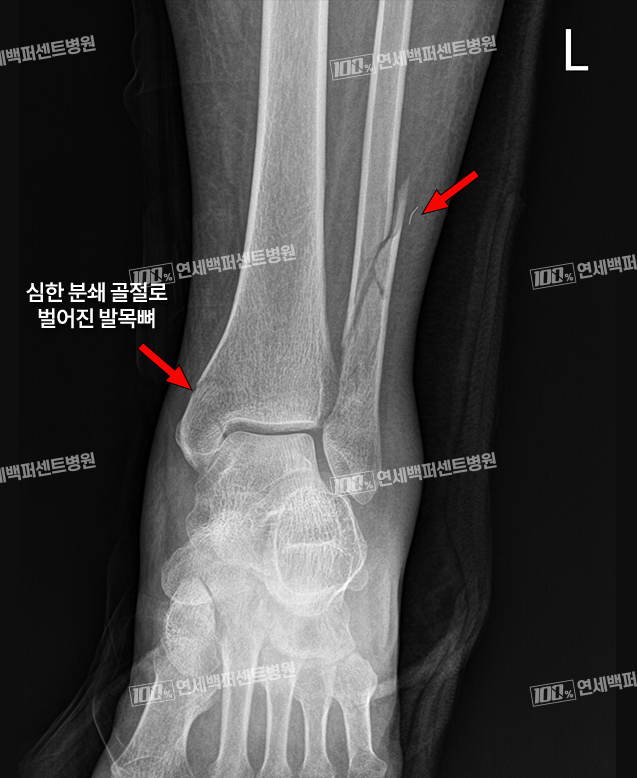

연세백퍼센트병원의

발/발목 골절 수술 사례

발/발목 골절 수술 전

하OO (22.10.15)

발/발목 골절 수술 후

하OO (23.01.14)